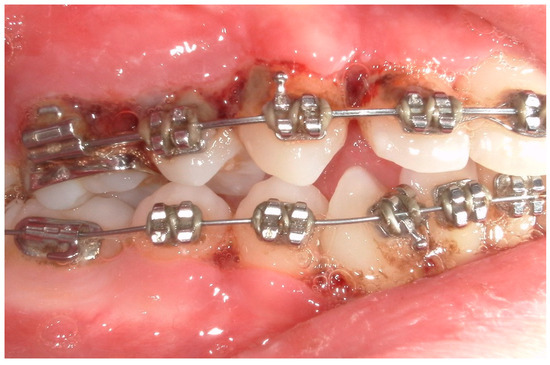

4. Clinical Cases

4.1. Case 1

4.2. Case 2